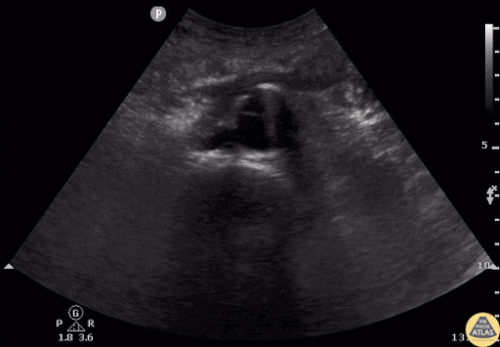

Ekokardiyografi (EKO): Normal Aort Örnekleri

Normal Aort Arkı – Suprasternal Görünüm

Normal Çölyak Trunkus ve SMA – Longitudinal

Normal Aort ve İliak Arterler – Transvers